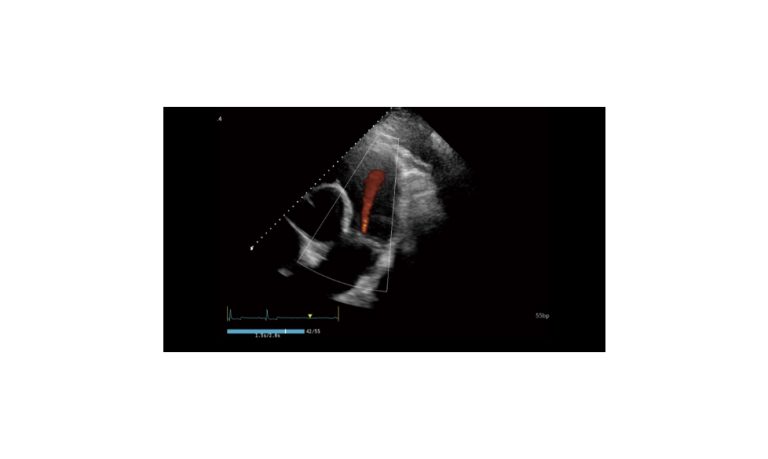

Ultrasound

Wide range of Ultrasound machines that suites a variety of applications from abdominal to rectal scans, we take in consideration how the world is moving towards mobility and mobile applications.

SonoScape Pro Pet E11

Smart Imaging

Introducing the first portable ultrasound with the C-Field+TM platform, redefining diagnostic imaging. Designed for veterinarians, it delivers unmatched clarity, ultra-fast processing, and seamless adaptability for all species. Experience Smart Imaging, Heartfelt Care—anywhere.

Equipped with cutting-edge veterinary software and optimized workflows, it embodies our commitment to Smart Imaging, Heartfelt Care – Wherever Their Journey Leads, with unparalleled performance and adaptability, this innovative system empowers veterinarians to provide exceptional care across all diagnostic applications,

EBIT50/60 VET

All the power you need

The EBit provides all the power you need for today´s challenging clinical environment, yet remain ultra-portable, ultra-affordable. With its cutting-edge imaging technologies, precise and intuitive workflow, ergonomic and eco-friendly design, versatile transducers for all applications from top to toe, we firmly believe the EBit to be the very best portable ultrasound in its class today.

ECO5 VET

Ultra-Portable, Ultra- Affordable, Color doppler

The multi-purpose user presets, comprehensive measurement & report system, built-in EasyView image achieve system, quick image storage / retrieve / transfer, one-button direct print, make the complete workflow better than what you can dream of.